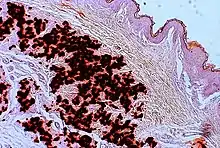

In PXE, there is mineralization (accumulation of calcium and other minerals) and fragmentation of the elastin-containing fibers in connective tissue, but primarily in the midlaminar layer of the dermis, Bruch's membrane and the midsized arteries.[26] Recent studies have confirmed that PXE is a metabolic disease, and that its features arise because metabolites of vitamin K cannot reach peripheral tissues.[27] Low levels of PPi cause mineralization in peripheral tissues.[19]

The diagnostic criteria for PXE are the typical skin biopsy appearance and the presence of angioid streaks in the retina. Criteria were established by consensus of clinicians and researchers at the 2010 biennial research meeting of the PXE Research Consortium.[29] and confirmed at the 2014 meeting[30] These consensus criteria state that definitive PXE is characterized by two pathogenic mutations in the ABCC6 or ocular findings – angioid streaks > 1 DD or peau d’orange in an individual <20 years of age together with skin findings:

- Diagnostic histopathological changes in lesional skin: Calcified elastic fibers in the mid and lower dermis, confirmed by positive calcium stain

| Pseudoxanthoma elasticum | LM: Mid-dermal calcification and fragmentation of elastic fibers EM: Mineralization in elastic fiber core |

| PXE-like papillary dermal elastolysis | LM: Selective elastic tissue elimination in the papillary dermis and presence of melanophages |